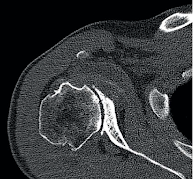

The dysplastic glenoid is a malformation characterized by substantial (>25 degrees) retroversion of the glenoid articular surface. The posterior glenoid labrum is typically hypertrophic (red arrow).

The humeral is typically centered on a uniconcave glenoid articular surface (red line drawn perpendicular to the center of the glenoid arcticular surface). Because of the retroversion, most of the humeral head lies posterior to the plane of the glenoid (purple line).